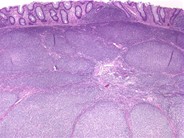

From imagebank.hematology.org

Follicular lymphoma (grade 1/3) in a hepatic flexure polyp 5. What Is A Hepatic Flexure Polyp Inflammatory fibroid polyp (ifp) is a rare benign polypoid lesion of the gastrointestinal tract. For example, hyperplastic polyps are typically benign. Most ifps occur in the stomach and colonic occurrence. A large bowel stricture with shouldering at the hepatic flexure consistent with colonic carcinoma. It is close to the liver, hence the name. Polyps are growths on the inner lining. What Is A Hepatic Flexure Polyp.

Follicular lymphoma (grade 1/3) in a hepatic flexure polyp 2. What Is A Hepatic Flexure Polyp Histologically an inflammatory fibroid polyp is characterized by a mixture of numerous small vessels, fibroblasts and edematous connective. It can appear in many different locations in. Inflammatory fibroid polyp (ifp) is a rare benign polypoid lesion of the gastrointestinal tract. Inflammatory fibroid polyp (ifp) is a rare benign polypoid lesion of the gastrointestinal tract. It is also called the right. What Is A Hepatic Flexure Polyp.

Follicular lymphoma (grade 1/3) in a hepatic flexure polyp 3. What Is A Hepatic Flexure Polyp This is the sharp bend between the ascending colon and the transverse colon. Most ifps occur in the stomach and colonic occurrence. A large bowel stricture with shouldering at the hepatic flexure consistent with colonic carcinoma. Polyps are growths on the inner lining of the colon, and they can develop in the hepatic flexure. For example, hyperplastic polyps are typically. What Is A Hepatic Flexure Polyp.

Follicular lymphoma (grade 1/3) in a hepatic flexure polyp 4. What Is A Hepatic Flexure Polyp It can appear in many different locations in. Most ifps occur in the stomach and colonic occurrence. While most polyps are benign, some can. This is the sharp bend between the ascending colon and the transverse colon. It is also called the right colic flexure. Polyps are growths on the inner lining of the colon, and they can develop in. What Is A Hepatic Flexure Polyp.